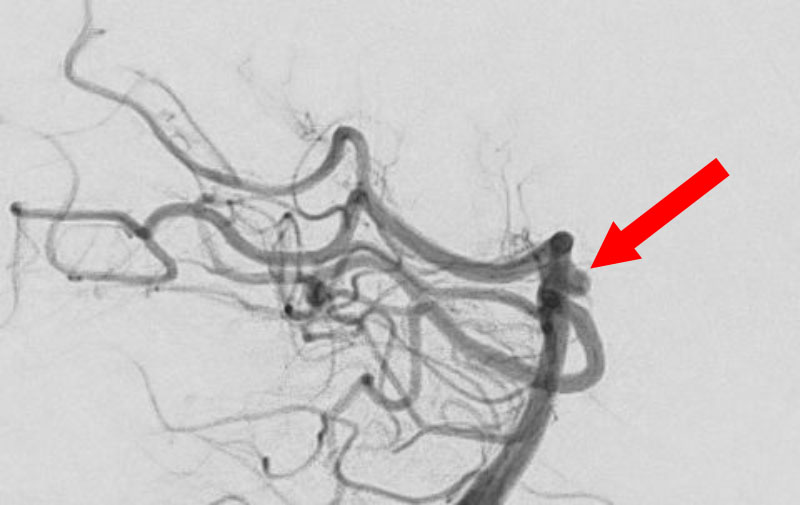

No.1592 手術前

No.1592 手術中

No.1592 手術後

くも膜下出血

右内頚動脈脳動脈瘤破裂

40代

救急外来